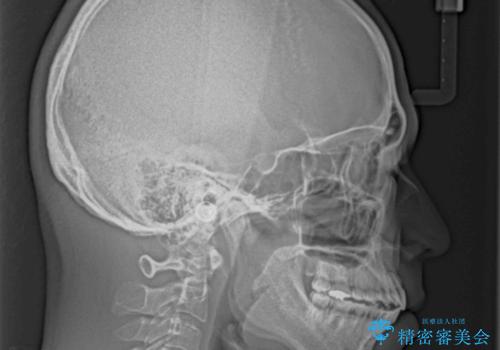

- 前歯の開咬と叢生を気にして来院された患者様です。

開咬の治療は、前歯を閉じるように動かすとともに、上下臼歯を圧下(骨内にめり込ませる)させることで進めて行きます。

インビザラインは臼歯の圧下を効果的に行えるため、インビザラインを用いて矯正治療を行うこととしました。また、アンカースクリューを用いて、口元の突出感の改善を図りました。